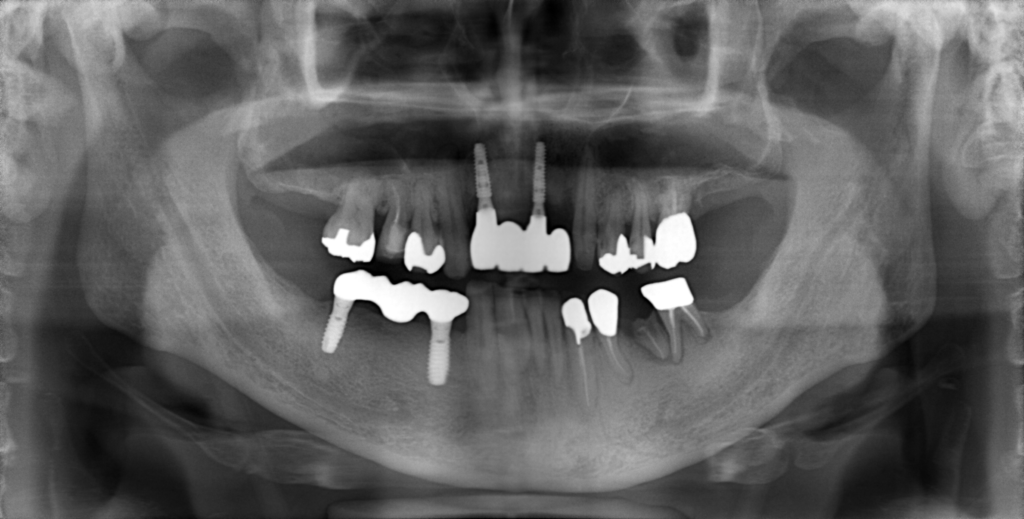

前歯の4本が、残すのが難しい状況となり、インプラント治療を行いました。

インプラントは前歯に2本埋入し、4本の前歯を作っています。歯を抜くと同時にインプラントを埋入し、仮歯を作りました。その後2ヶ月で、被せ物を入れました。被せ物は、セラミックスで作っています。

治療前

治療後